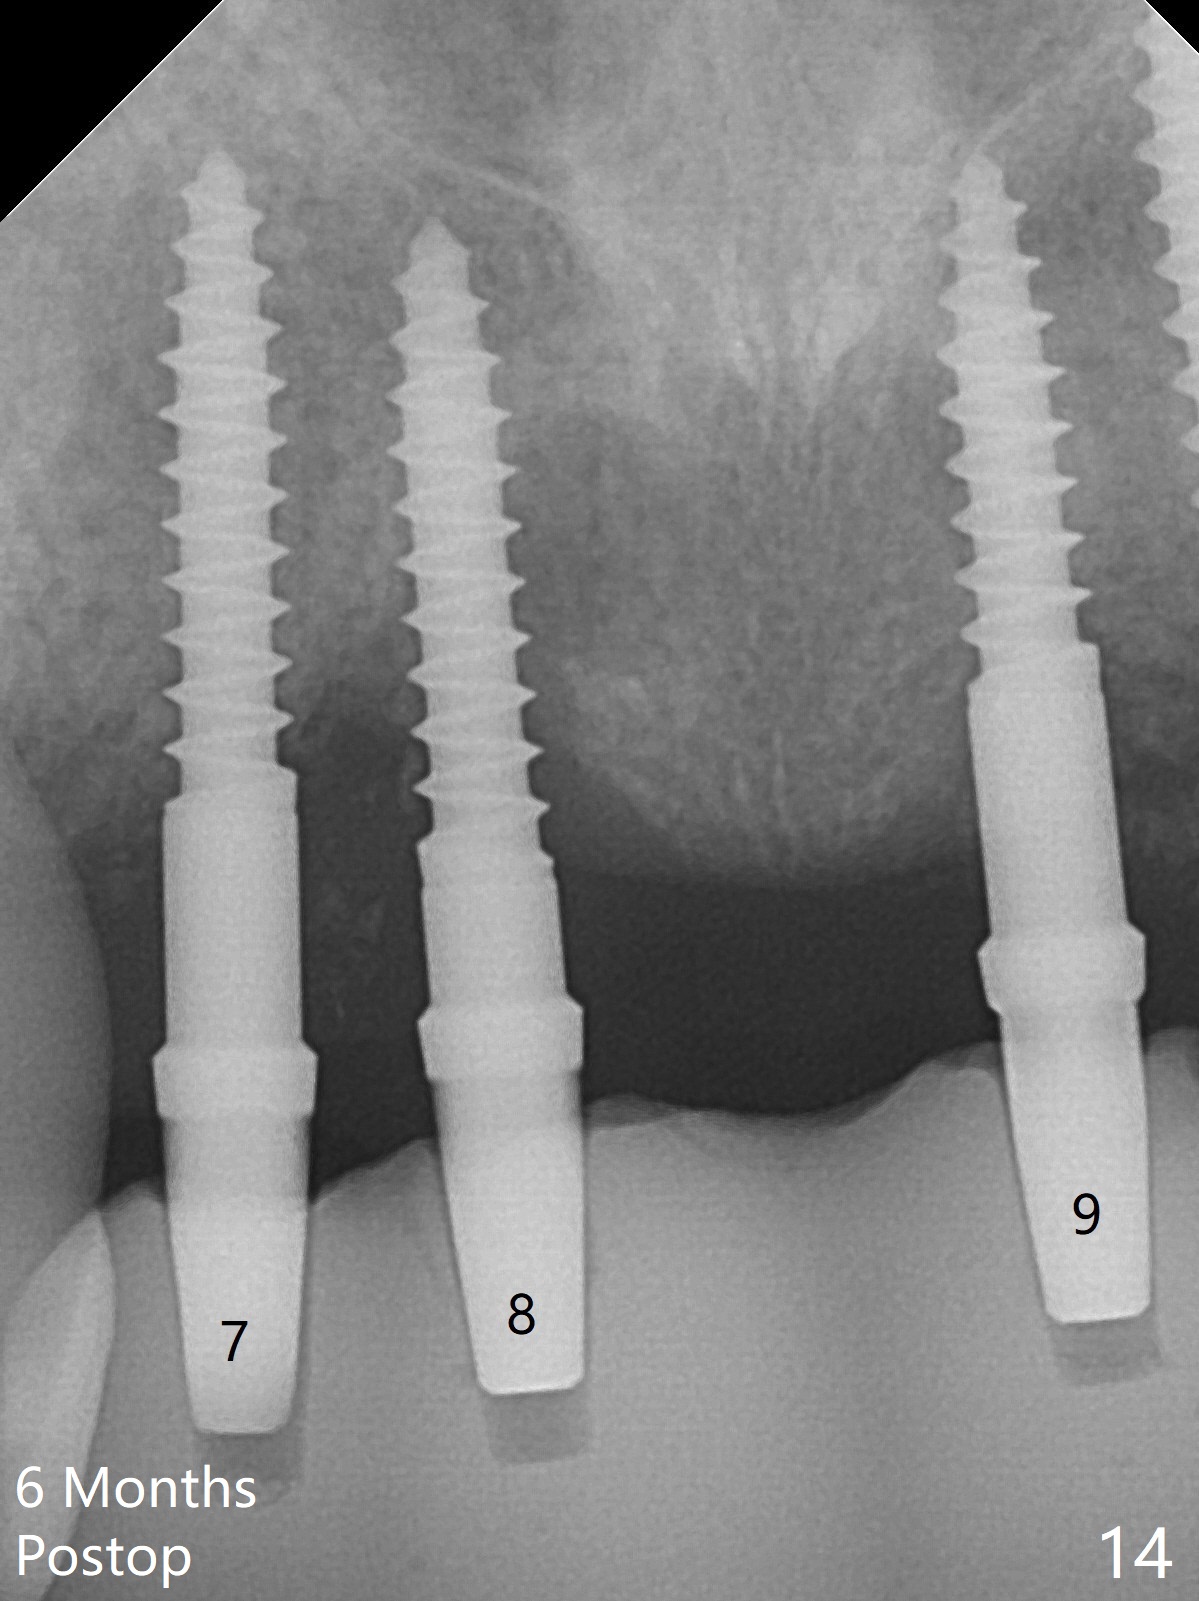

Although the ridge of the maxillary anterior ridge looks moderate in width (Fig.1), the bone is ~4 mm buccopalatally. Suction down surgical stent (Fig.2') made from the lab-fabricated provisional (Fig.2) will be used to check the position and trajectory of osteotomies. PAs taken after initial osteotomies (1.2 mm drill) show those at the central incisors tend to be mesial (close to the Incisive Canal *), while those at the lateral incisor sites distal (Fig.3,4). After adjustment, the position and trajectory of the osteotomies are acceptable (Fig.5,6). To reduce the chance of perforating the Incisive Canal (Fig.3,4 *), 2.5 mm 1-piece implants are inserted with >40 Ncm (Fig.7,8). After deep placement of the implants, Vanilla graft is placed at the crest (Fig.9,10 *). An immediate splinted provisional is fabricated from the suction down stent. The gingiva is healthy around the provisional (Fig.11) and the implants (Fig.12,13) 1 month postop. The provisional is adjusted monthly so that the interdental papillae can be elongated. No bone resorption is observed 6 months postop (Fig.14,15). Crowns are cemented 8 months postop (Fig.16-18). The keratinized gingiva appears to have formed the abutments 8 months postop immediately pre-cementation (Fig.19).